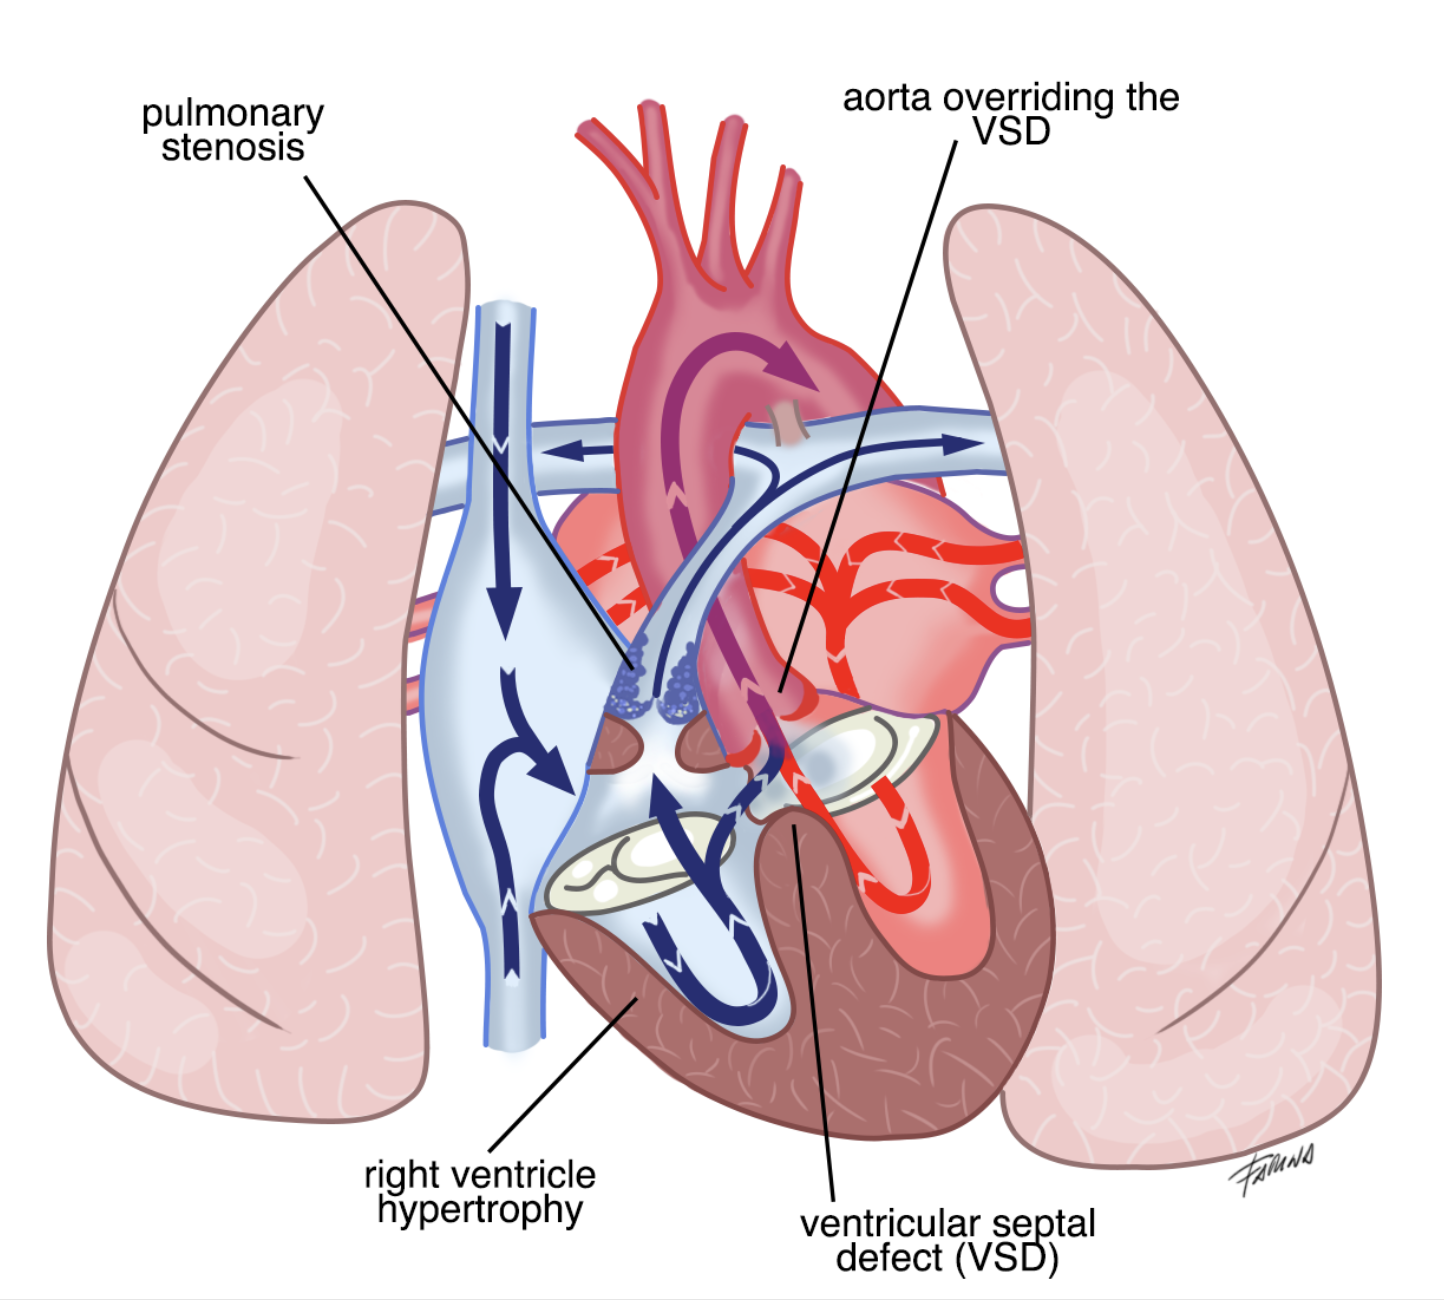

La tetralogia di Fallot è la più comune cardiopatia congenita in grado di causare cianosi, colorazione bluastra di cute e mucose. E’ caratterizzata da quattro componenti fondamentali, evidenziate nell’immagine: difetto interventricolare (una comunicazione anomala tra i due ventricoli), posizione dell’aorta a cavallo tra i due ventricoli e immediatamente sopra il difetto, restringimento della valvola polmonare e del tratto muscolare al di sotto di essa e ipertrofia (irrobustimento) del ventricolo destro.

Durante la contrazione dei ventricoli, il sangue in ventricolo destro (venoso e povero in ossigeno) ha a disposizione una strada a minor resistenza rispetto a quella fisiologica: può infatti passare attraverso il difetto interventricolare ed essere eiettato dal ventricolo sinistro in aorta. Di conseguenza, la concentrazione di ossigeno nel sangue arterioso risulterà ridotta in modo proporzionale alla gravità della patologia e/o in relazione a fenomeni transitori di aumento delle resistenze polmonari (pianto, stress, sforzo fisico, defecazione, febbre). L’eccesso di emoglobina deossigenata causa la colorazione bluastra di cute e mucose (cianosi). Da qui il nome di “sindrome del bambino blu”.